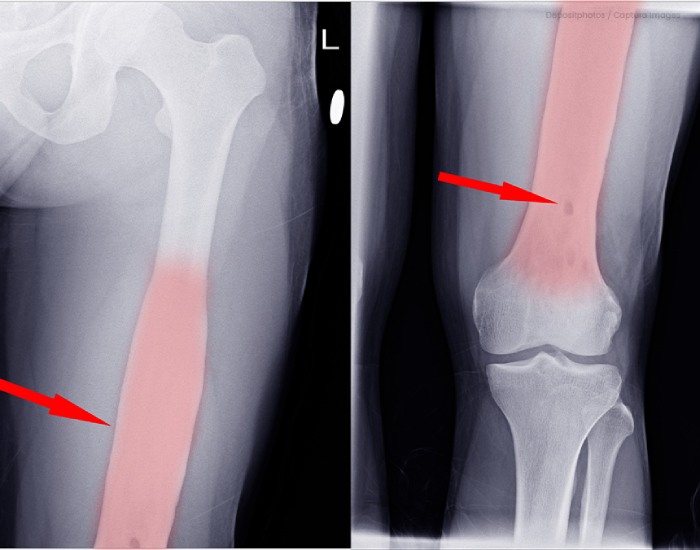

La enfermedad que padece el presidente, conocida técnicamente como osteomielitis, es una infección que afecta tanto al tejido óseo como a la médula. En este caso particular, la infección se ha localizado en los huesos de la pelvis (ilion, isquion o pubis), una variante especialmente rara y compleja. El origen del proceso ha sido identificado como la bacteria Streptococcus dysgalactiae, aunque los médicos recuerdan que, en términos generales, la causa más común de cualquier tipo de infección ósea suele ser el Staphylococcus aureus, una bacteria presente de forma natural en nuestra piel.

El riesgo de esta dolencia reside en su capacidad para pasar desapercibida en sus etapas iniciales. Al afectar a estructuras internas como el pubis, el dolor puede confundirse fácilmente con una lesión muscular o una dolencia articular común. Sin embargo, la osteomielitis demanda una intervención rápida; de lo contrario, la bacteria puede causar daños estructurales permanentes en el hueso o extenderse a tejidos adyacentes, complicando gravemente el pronóstico del paciente.